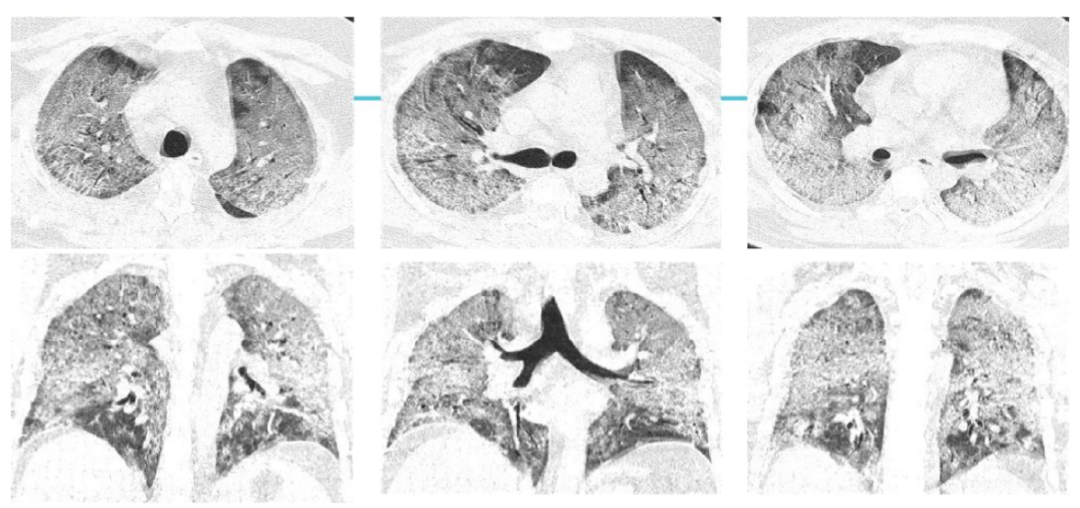

案例三,30歲,男性,確診病例

影像所見:發(fā)熱12天,胸悶、氣喘7天。胸部CT顯示兩肺彌散性磨玻璃影,呈“白肺”改變,其內(nèi)可見空氣支氣管征、雙側(cè)膈面上抬。